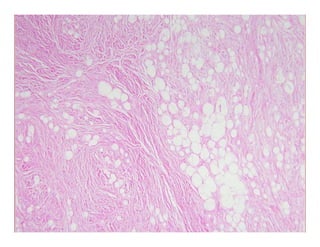

Lobular panniculitis, c/w ErythemaLobular panniculitis, c/w Erythema

i di dinduratuminduratum

In lobular panniculitides, inflammatory infiltrate isIn lobular panniculitides, inflammatory infiltrate is

t th h t th l b l BUT th i ftt th h t th l b l BUT th i ftpresent throughout the lobule…BUT, there is often somepresent throughout the lobule…BUT, there is often some

septal involvement as well.septal involvement as well.

Nodular vasculitis/Erythema induratumNodular vasculitis/Erythema induratum

–– Originally 1 entity, then 2 (Bazin, Whitfield), now one again?Originally 1 entity, then 2 (Bazin, Whitfield), now one again?

–– Appears to be a disease of diverse etiologiesAppears to be a disease of diverse etiologies

Lobular or septolobular panniculitis… with:Lobular or septolobular panniculitis… with:

–– Granulomatous inflammationGranulomatous inflammation –– usually poorly developed, ALSOusually poorly developed, ALSO

with neutrophils lymphocytes and some plasma cellswith neutrophils lymphocytes and some plasma cellswith neutrophils, lymphocytes, and some plasma cellswith neutrophils, lymphocytes, and some plasma cells

–– VasculitisVasculitis

–– NecrosisNecrosis

–– Septal fibrosisSeptal fibrosis–– Septal fibrosisSeptal fibrosis

Lobular panniculitis, c/wErythemaLobular panniculitis, c/w Erythema i di dinduratuminduratum In lobular panniculitides, inflammatory infiltrate isIn lobular panniculitides, inflammatory infiltrate is t th h t th l b l BUT th i ftt th h t th l b l BUT th i ftpresent throughout the lobule…BUT, there is often somepresent throughout the lobule…BUT, there is often some septal involvement as well.septal involvement as well. Nodular vasculitis/Erythema induratumNodular vasculitis/Erythema induratum –– Originally 1 entity, then 2 (Bazin, Whitfield), now one again?Originally 1 entity, then 2 (Bazin, Whitfield), now one again? –– Appears to be a disease of diverse etiologiesAppears to be a disease of diverse etiologies Lobular or septolobular panniculitis… with:Lobular or septolobular panniculitis… with: –– Granulomatous inflammationGranulomatous inflammation –– usually poorly developed, ALSOusually poorly developed, ALSO with neutrophils lymphocytes and some plasma cellswith neutrophils lymphocytes and some plasma cellswith neutrophils, lymphocytes, and some plasma cellswith neutrophils, lymphocytes, and some plasma cells –– VasculitisVasculitis –– NecrosisNecrosis –– Septal fibrosisSeptal fibrosis–– Septal fibrosisSeptal fibrosis